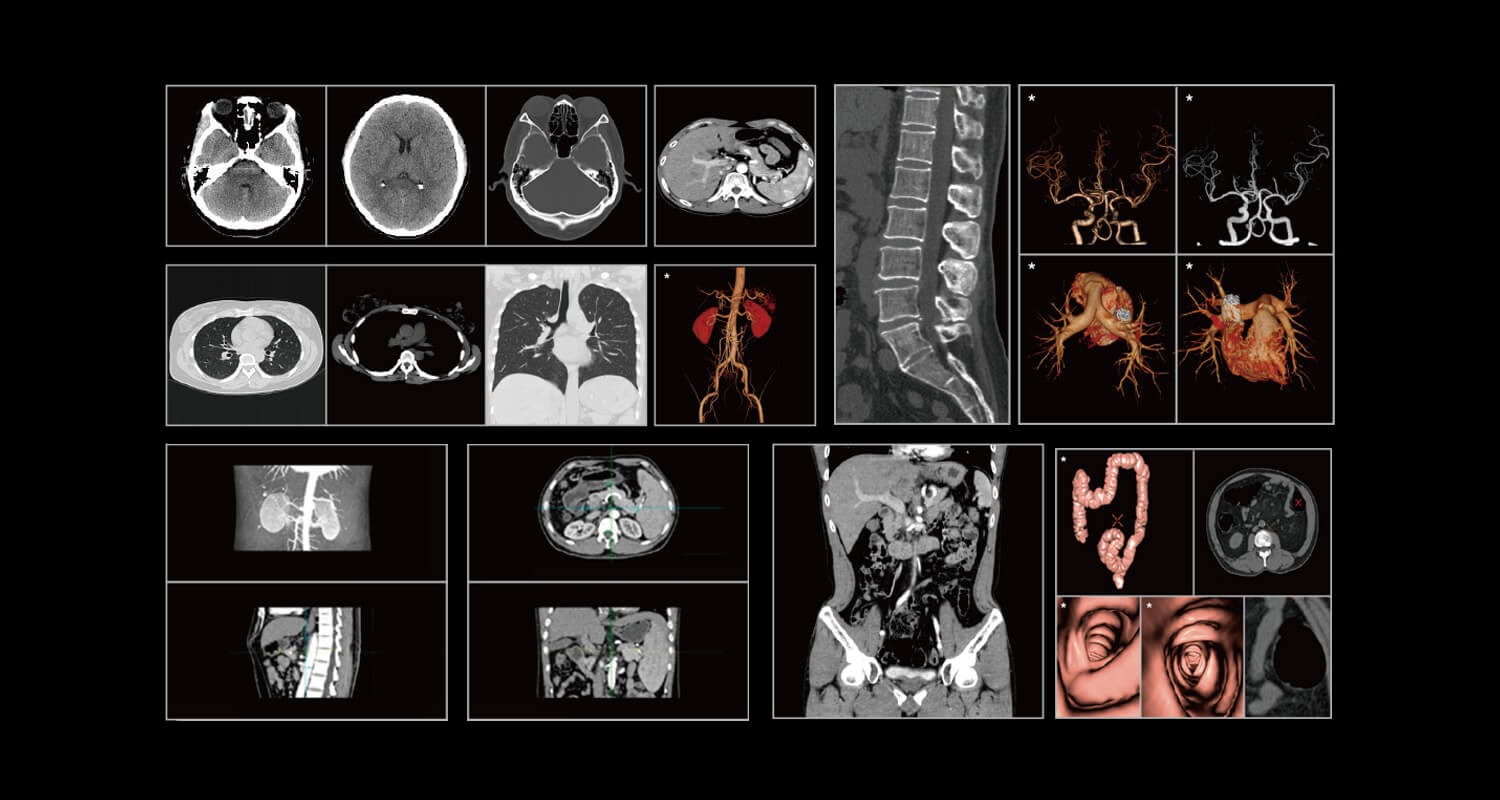

臨床畫(huà)廊